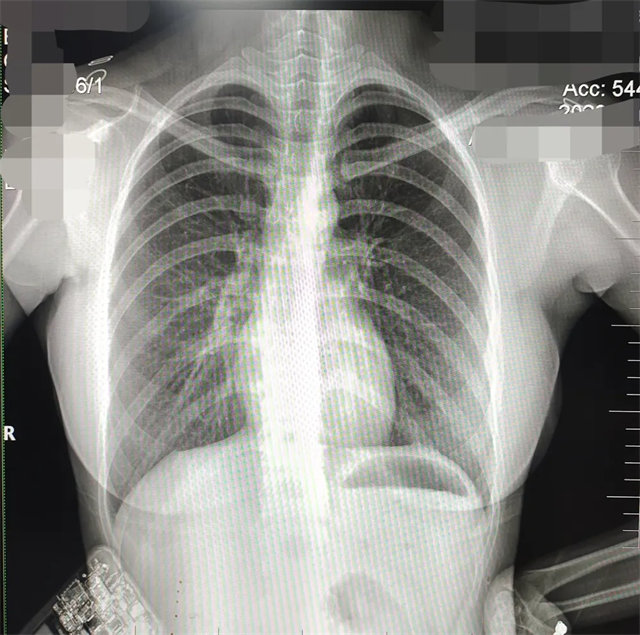

拍攝的不合格胸片的缺陷和解決方法

缺陷:雙側(cè)胸鎖關(guān)節(jié)不對稱,且有手機顯影。

解決:去除手機后,使患者左側(cè)緊貼成像件曝光。